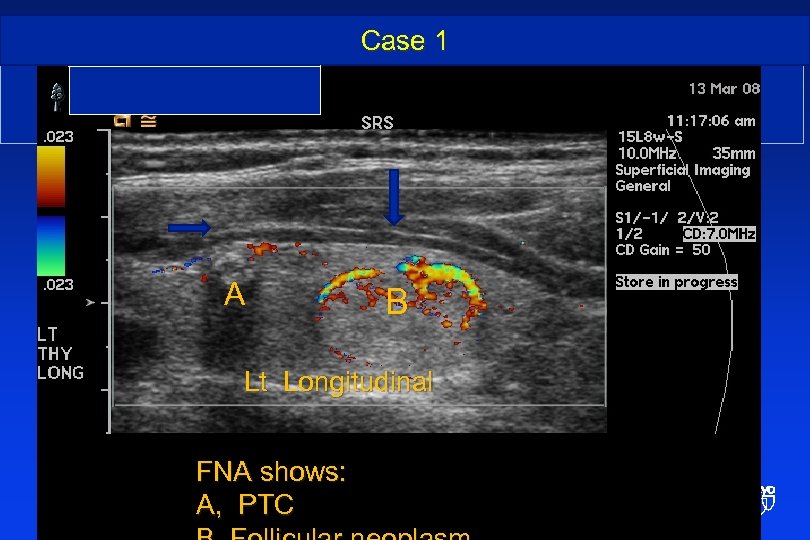

Case 1 Incidental PTC and benign thyroid nodule • . A B Lt Longitudinal FNA shows: A, PTC